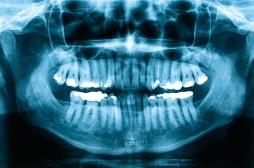

densité osseuse